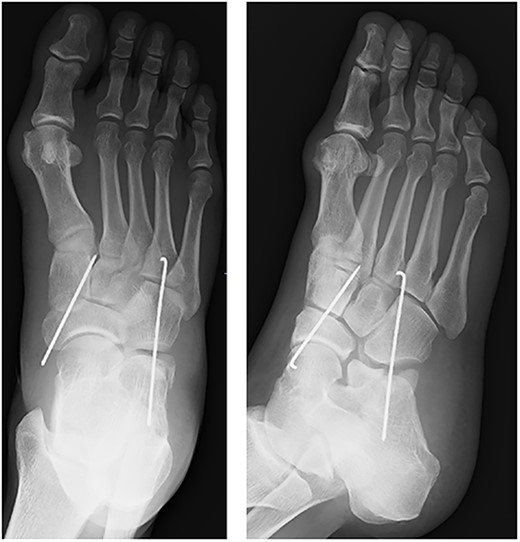

A 57-year-old carpenter fell from a height of 6 m and hit the right half of his body. He visited the emergency department of our hospital the same day. Physical examination revealed tenderness, swelling and deformity in the right foot (Fig. 1). Plain radiography, computed tomography (CT) and three-dimensional (3D) CT showed an uncommon injury; lateral dislocation of the naviculocuneiform joint, lateral dislocation of the calcaneocuboid joint, compression fracture of the calcaneus and avulsion fracture of the cuboid in the right foot (Figs 2 and 3). The next day, we attempted closed reduction, but the reduction was unstable. Percutaneous fixation with Kirschner wires (K-wires) was performed to stabilize the dislocated fragments. Two 1.5-mm K-wires were inserted from the navicular and cuboid bones to the medial cuneiform and calcaneus bones, respectively, and the dislocated joints were stabilized (Fig. 4). Postoperatively, the foot was immobilized with a below-knee splint. Mild ankle exercise was initiated in the early postoperative phase. The K-wires were removed at 8 weeks. Full weight-bearing was started at 14 weeks, and he was able to walk without pain. At 19 weeks, he returned to his job. At 1 year after the operation, the American Orthopaedic Foot and Ankle Society midfoot score was 75/100 points. He had mild and occasional pain, but he could walk about 2000 steps consecutively with no support or difficulty, and he had no marked limitation of daily activities. Fracture dislocation sites were stable on plain radiography (Fig. 5).

After fixation with K-wires. The dislocated site is reduced and stabilized.

Plain radiograph at 1 year after the initial operation. There was no marked malalignment in the right foot.